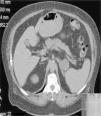

The results suggested an ovarian tumor and we ordered a vaginal ultrasound, which revealed no alterations. The patient was referred to the endocrinology department for further testing, including tumor marker and imaging tests. Prolactin and cortisol tests were normal, as were the results for all tumor markers analyzed except carcinoembryonic antigen, with a level of 14.5ng/mL (normal range, 0-5ng/mL). An abdominal computed tomography scan showed images consistent with a left adrenal tumor (Fig. 3). Magnetic resonance imaging of the pelvis showed no signs of an ovarian tumor. With these findings, it was decided to perform a left adrenalectomy, but the patient continued to show high testosterone levels (4.06ng/mL; normal range, 0.20-0.80) and a high free testosterone index (42.6; normal range, 1.6-6) after the operation. Finally, given the strong suspicion of hyperandrogenism of ovarian origin, we performed a bilateral adnexectomy.